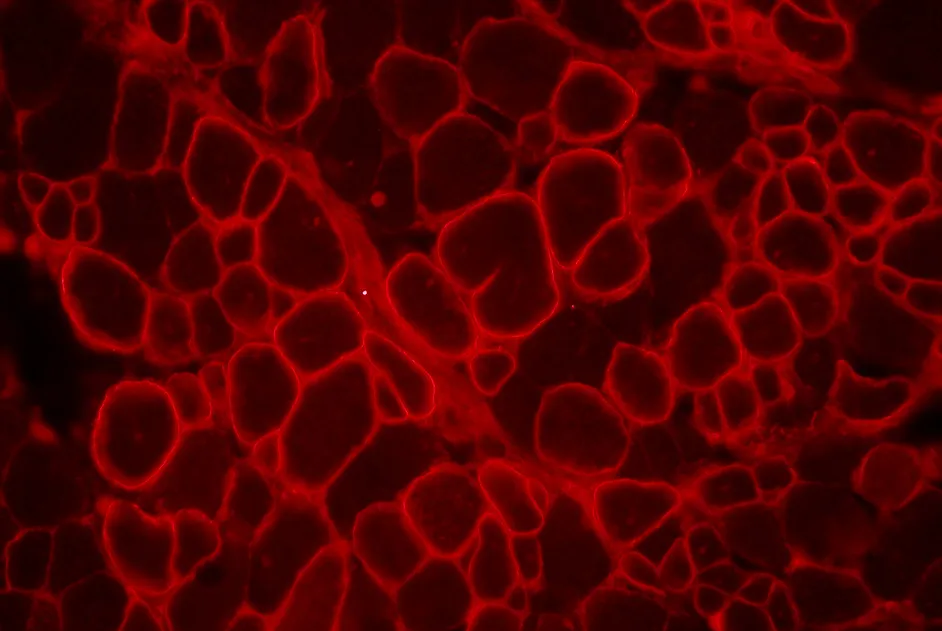

Myopathie de Duchenne et réponse immunitaire à la dystrophine

Le risque d'une réponse immunitaire contre la dystrophine dans la myopathie de Duchenne augmente avec l'âge et est diminué sous corticoïdes.